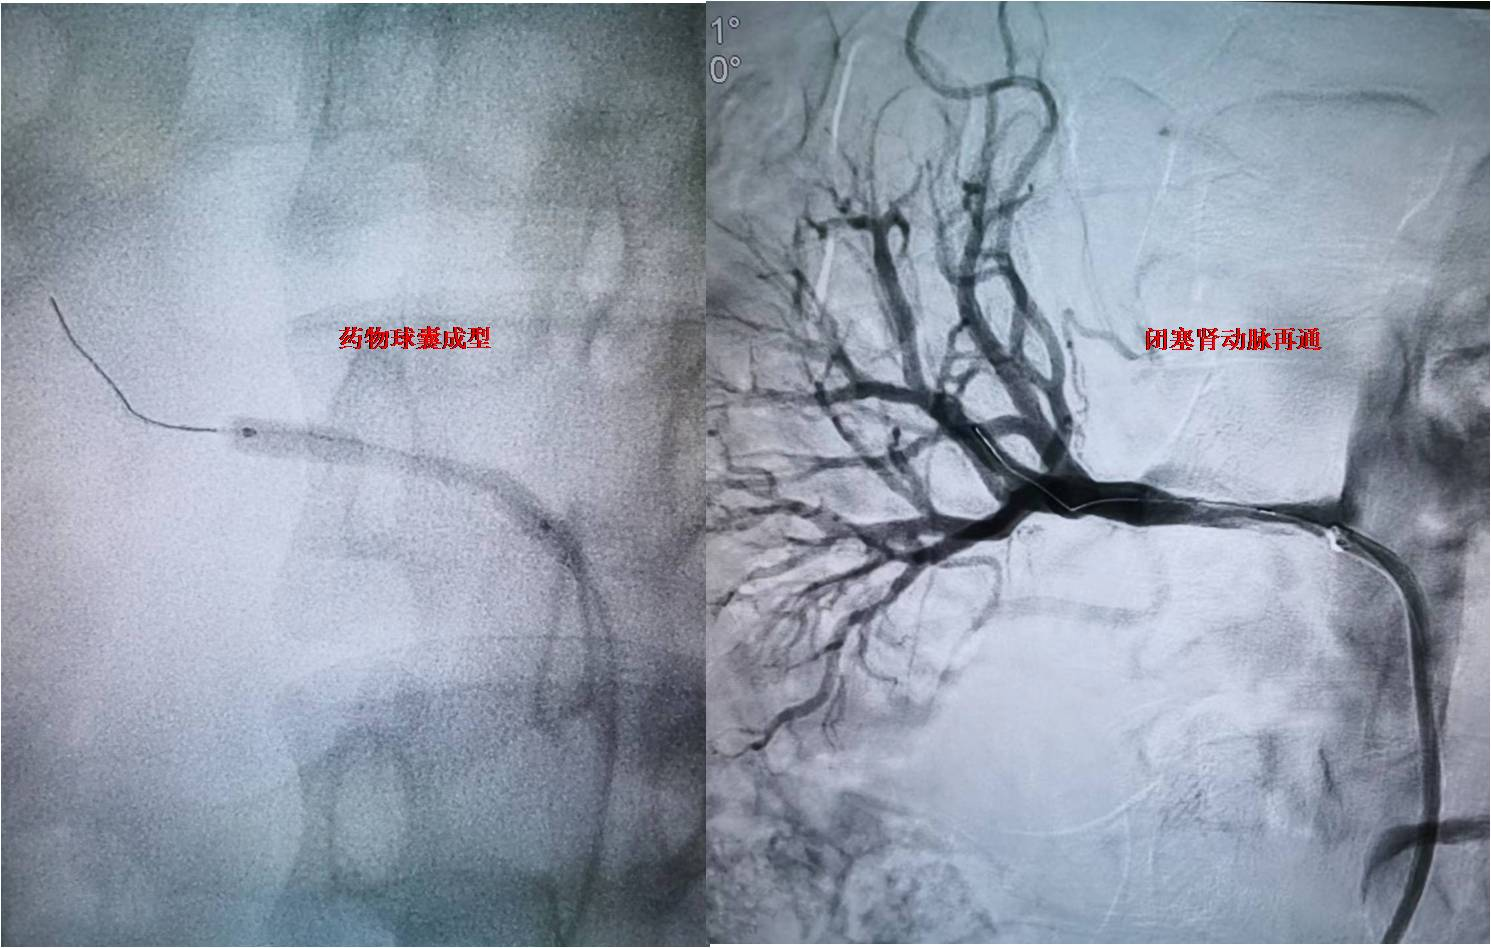

图-3 闭塞肾动脉再通

患者为未成年男性,在当地因高血压病就诊检查,发现存在肾动脉狭窄可能,患者血压最高达200/146mmHg,为进一步诊治,来到西安交大一附院血管外科杨林教授门诊。患者入院后,杨林教授及诊疗团队韩阳医师、武士琪医师、李小兵医师对其进行了完善的术前检查、术前准备及药物治疗。进一步明确患者为肾动脉闭塞,手术难度极大,手术风险极高。考虑到患者未成年,为保留患者潜在的肾功能,同时避免采用常规的金属支架技术,杨林教授团队经过详细的术前讨论和设计手术方案后,决定给患者实施局麻微创的药物球囊成型技术。在介入手术室的配合下,发现患者为右肾动脉闭塞,远端通过毛细血管代偿,手术团队通过精细的微创技术,反复尝试都未能通过闭塞段血管,最后通过各种微导丝、微导管技术的联合应用终于通过闭塞的肾动脉,然后通过小球囊预扩张,过渡到常规球囊扩张,最后为患者实施药物球囊扩张成形术,患者闭塞的肾动脉得到完美重建。患者术后在血管外科医护团队的严密监控下顺利恢复。术后血压即恢复正常,于近日顺利出院。